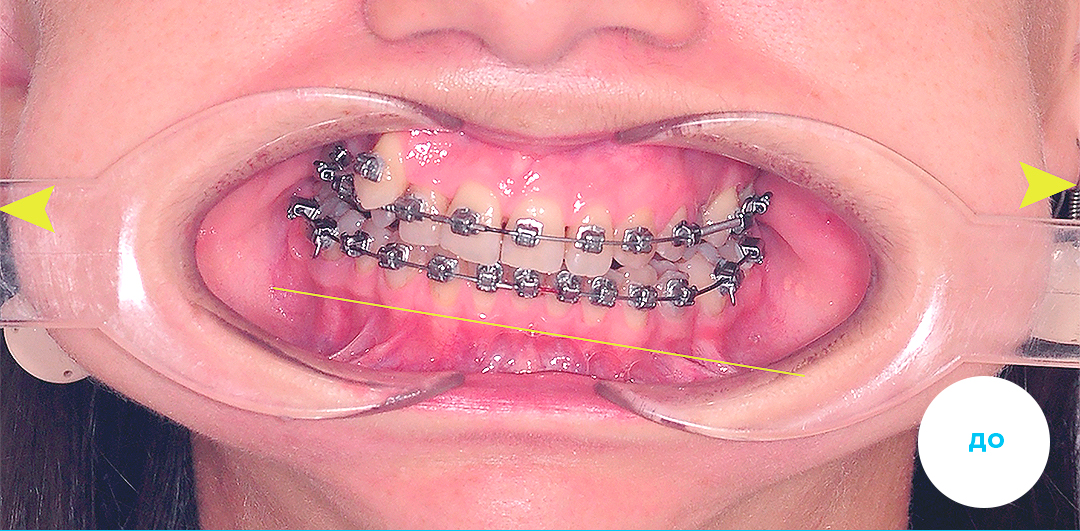

До

После

Ортодонтическое лечение подростка металлическими брекетами на 1 челюсти и аппаратом Гербста